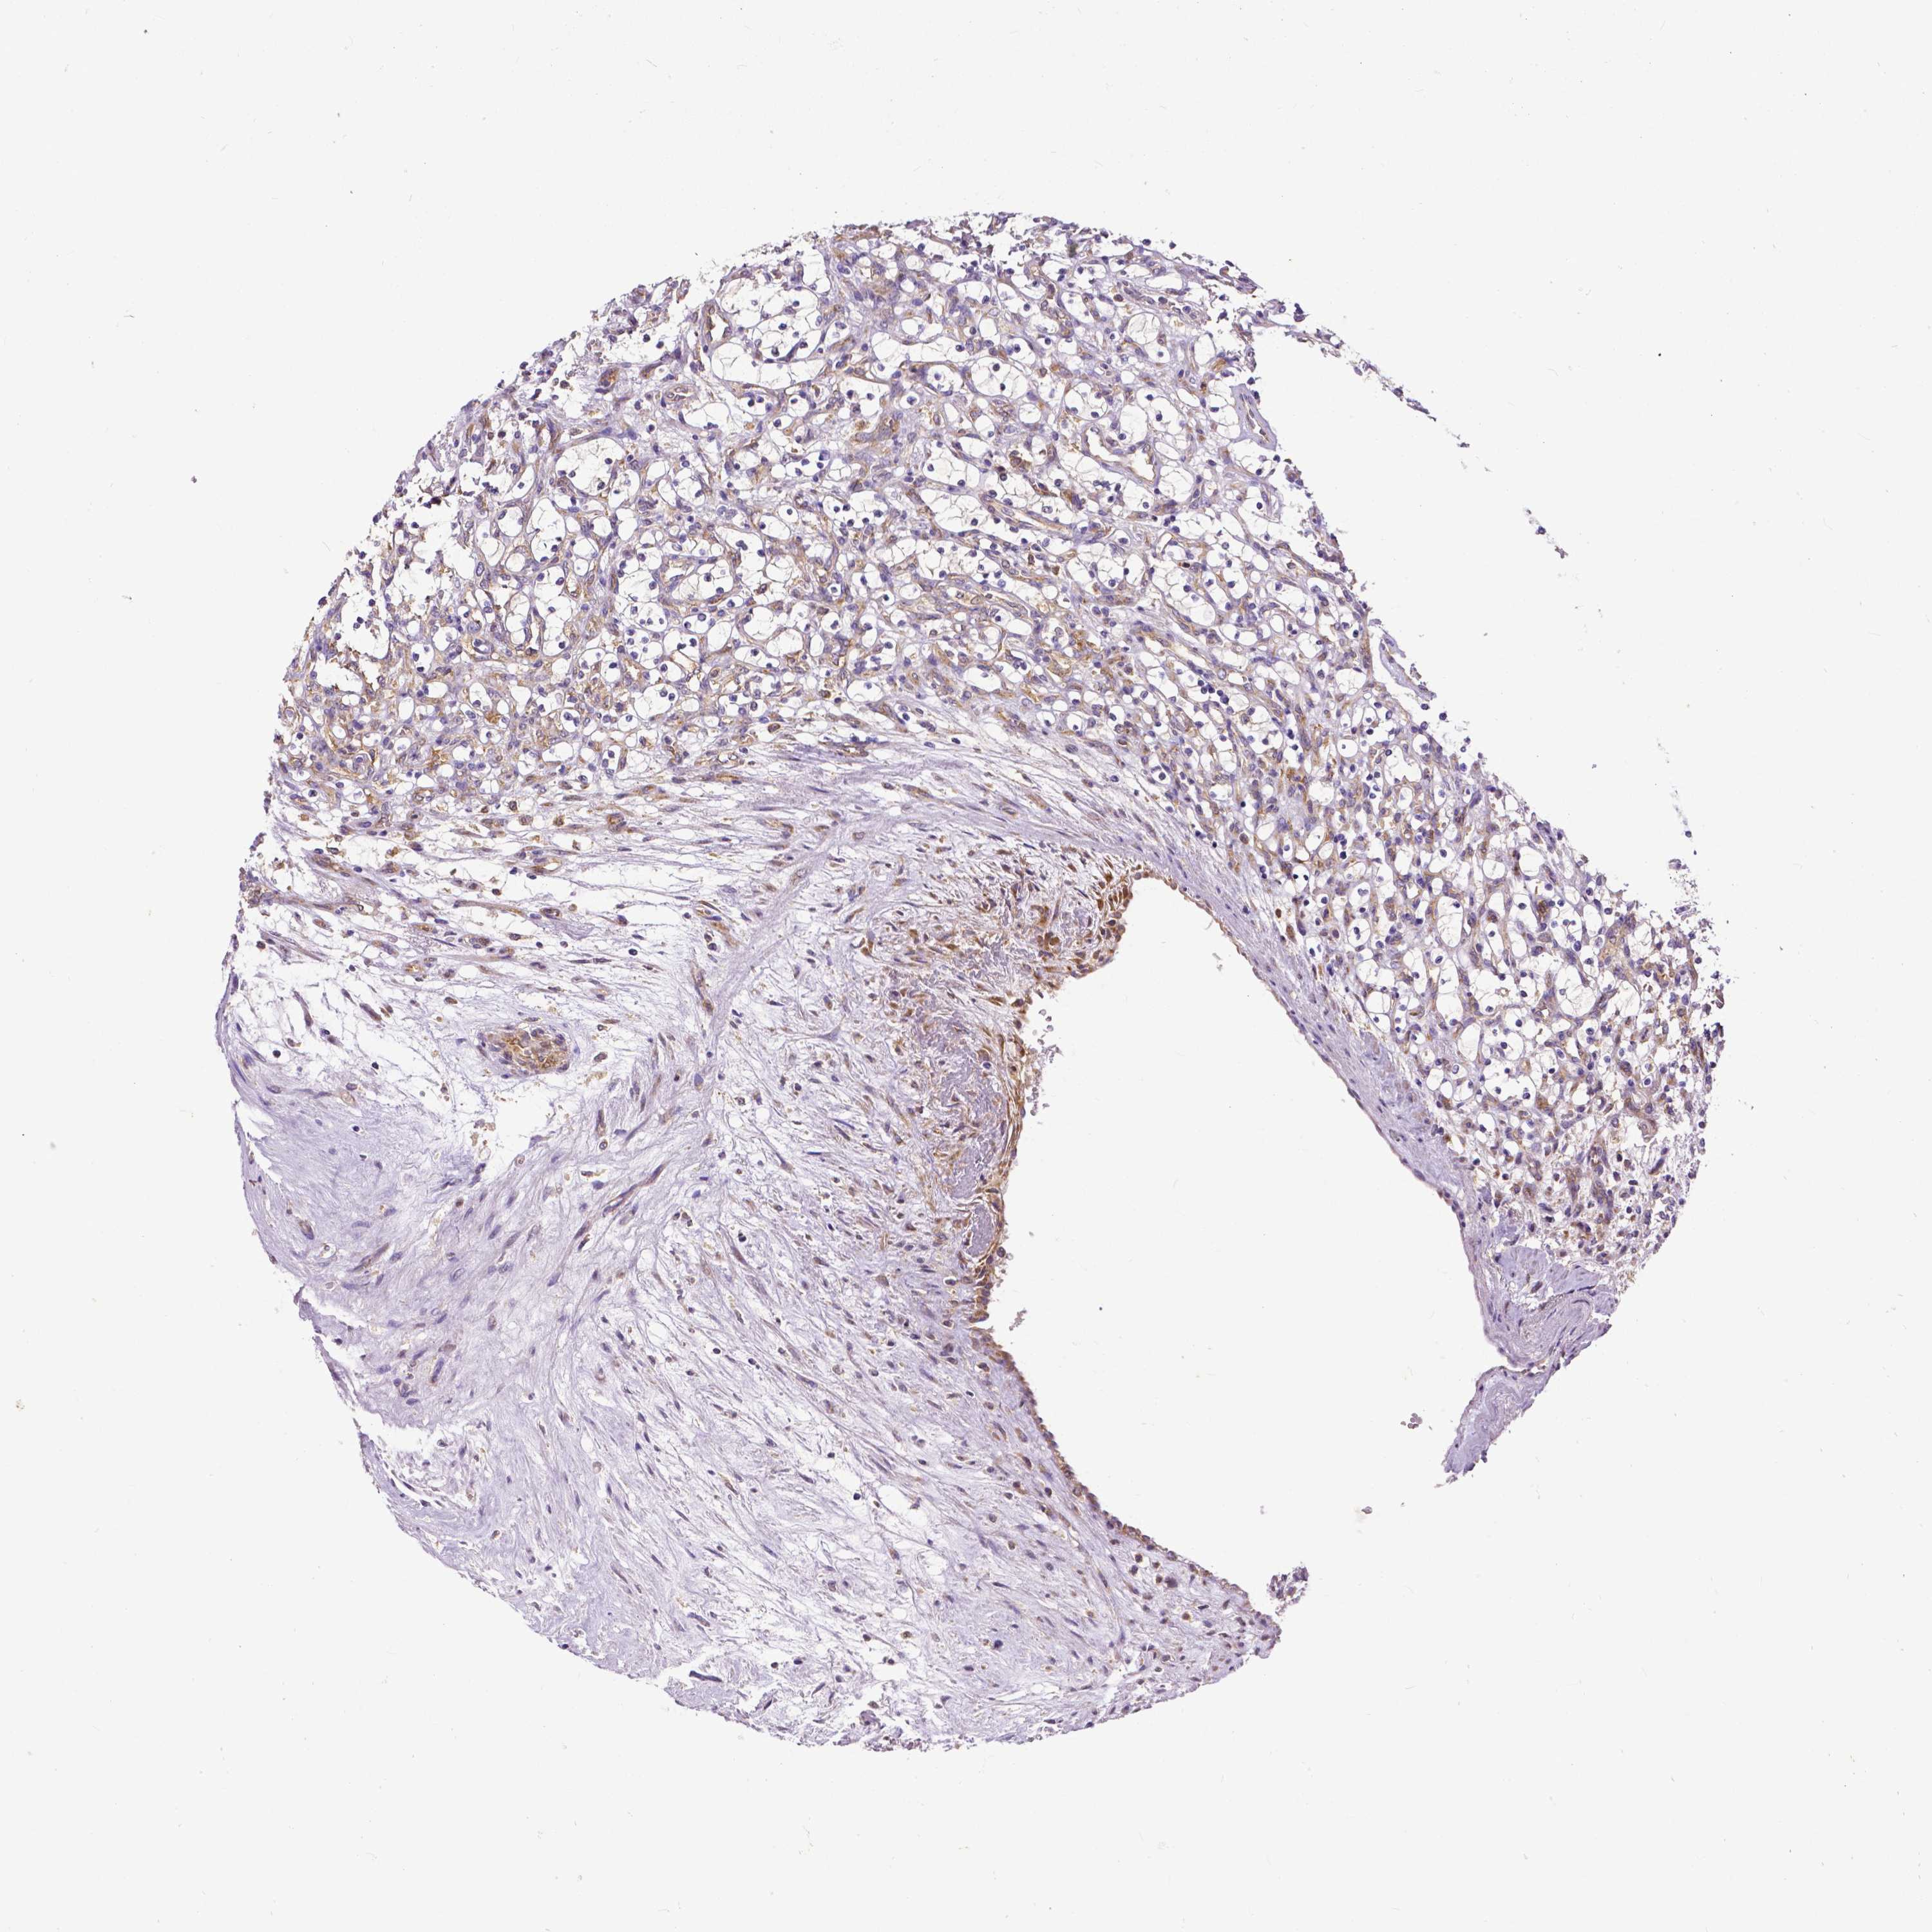

KIDNEY RENAL CLEAR CELL CARCINOMA (VALIDATION) - Interactive survival scatter ploti

The Survival Scatter plot shows the clinical status (i.e. dead or alive) for all individuals in the patient cohort, based on the same data that underlies the corresponding Kaplan-Meier plots. Patients that are alive at last time for follow-up are shown in blue and patients who have died during the study are shown in red.

The x-axis shows the expression levels (FPKM) of the investigated gene in the tumor tissue at the time of diagnosis. The y-axis shows the follow-up time after diagnosis (years). Both axes are complimented with kernel density curves demonstrating the data density over the axes. The top density plot shows the expression levels (FPKM) distribution among dead (red) and alive patients (blue). The right density plot shows the data density of the survived years of dead patients with high and low expression levels respectively, stratified using the cutoff indicated by the vertical dashed line through the Survival Scatter plot. This cutoff is automatically defined based on the FPKM cutoff that minimizes the p-score. The cutoff can be changed by dragging the vertical line or by entering a cutoff value in the square labeled "Current cut-off".

Under the Survival Scatter plot the p-score landscape (black curve; left axis) is shown together with dead median separation (red curve; right axis). Dead median separation is the difference in median mRNA expression between patients who have died with high and low expression, respectively. It is calculated as follows: median FPKM expression of dead patients with high expression - median FPKM expression of dead patients with low expression. This is intended to aid the user in visually exploring custom cutoffs and the associated p-scores and dead median separation.

Individual patient data is displayed and can be filtered by clicking on one or more of the category buttons on the top of the page. Categories describing expression level and patient information include: high, low, alive, dead, female, male and tumor stages. The scale of the x-axis can be toggled between linear and log-scale by clicking on the "x log" button. Mouse-over function shows TCGA ID, patient information and mRNA expression (FPKM) for each patient.

& Survival analysisi

Kaplan-Meier plots summarize results from analysis of correlation between mRNA expression level and patient survival. Patients were divided based on level of expression into one of the two groups "low" (under cut off) or "high" (over cut off). X-axis shows time for survival (years) and y-axis shows the probability of survival, where 1.0 corresponds to 100 percent.

DICER1 is not prognostic in Kidney Renal Clear Cell Carcinoma (validation)

Best expression cut offi

Based on the FPKM value of each gene, patients were classified into two groups and association between prognosis (survival) and gene expression (FPKM) was examined. The best expression cut-off refers the FPKM value that yields maximal difference with regard to survival between the two groups at the lowest log-rank P-value. Best expression cut-off was selected based on survival analysis .

When clicking on this number, the vertical dashed line indicating cut-off, the interactive survival plot, and the Kaplan-Meier curve will be adjusted to show results based on the best expression cut-off.

: 15.26

TCGA RNA samplesi

RNA-seq data is reported as average FPKM (number Fragments Per Kilobase of exon per Million reads), generated by the The Cancer Genome Atlas (TCGA) .

Normal distribution across the dataset is visualized with box plots, shown as median and 25th and 75th percentiles. Points are displayed as outliers if they are above or below 1.5 times the interquartile range. FPKM values of the individual samples are presented next to the box plot.

Average pTPM 10.2

Number of samples 100